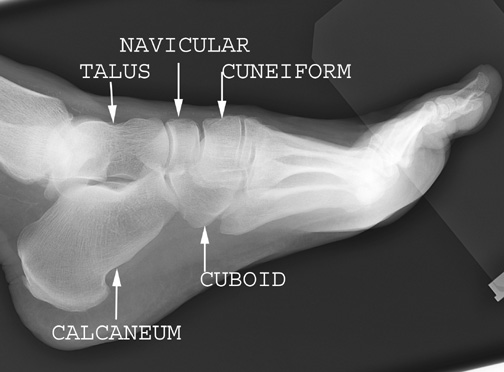

Identify the tarsal bones. Click the image for labeling.